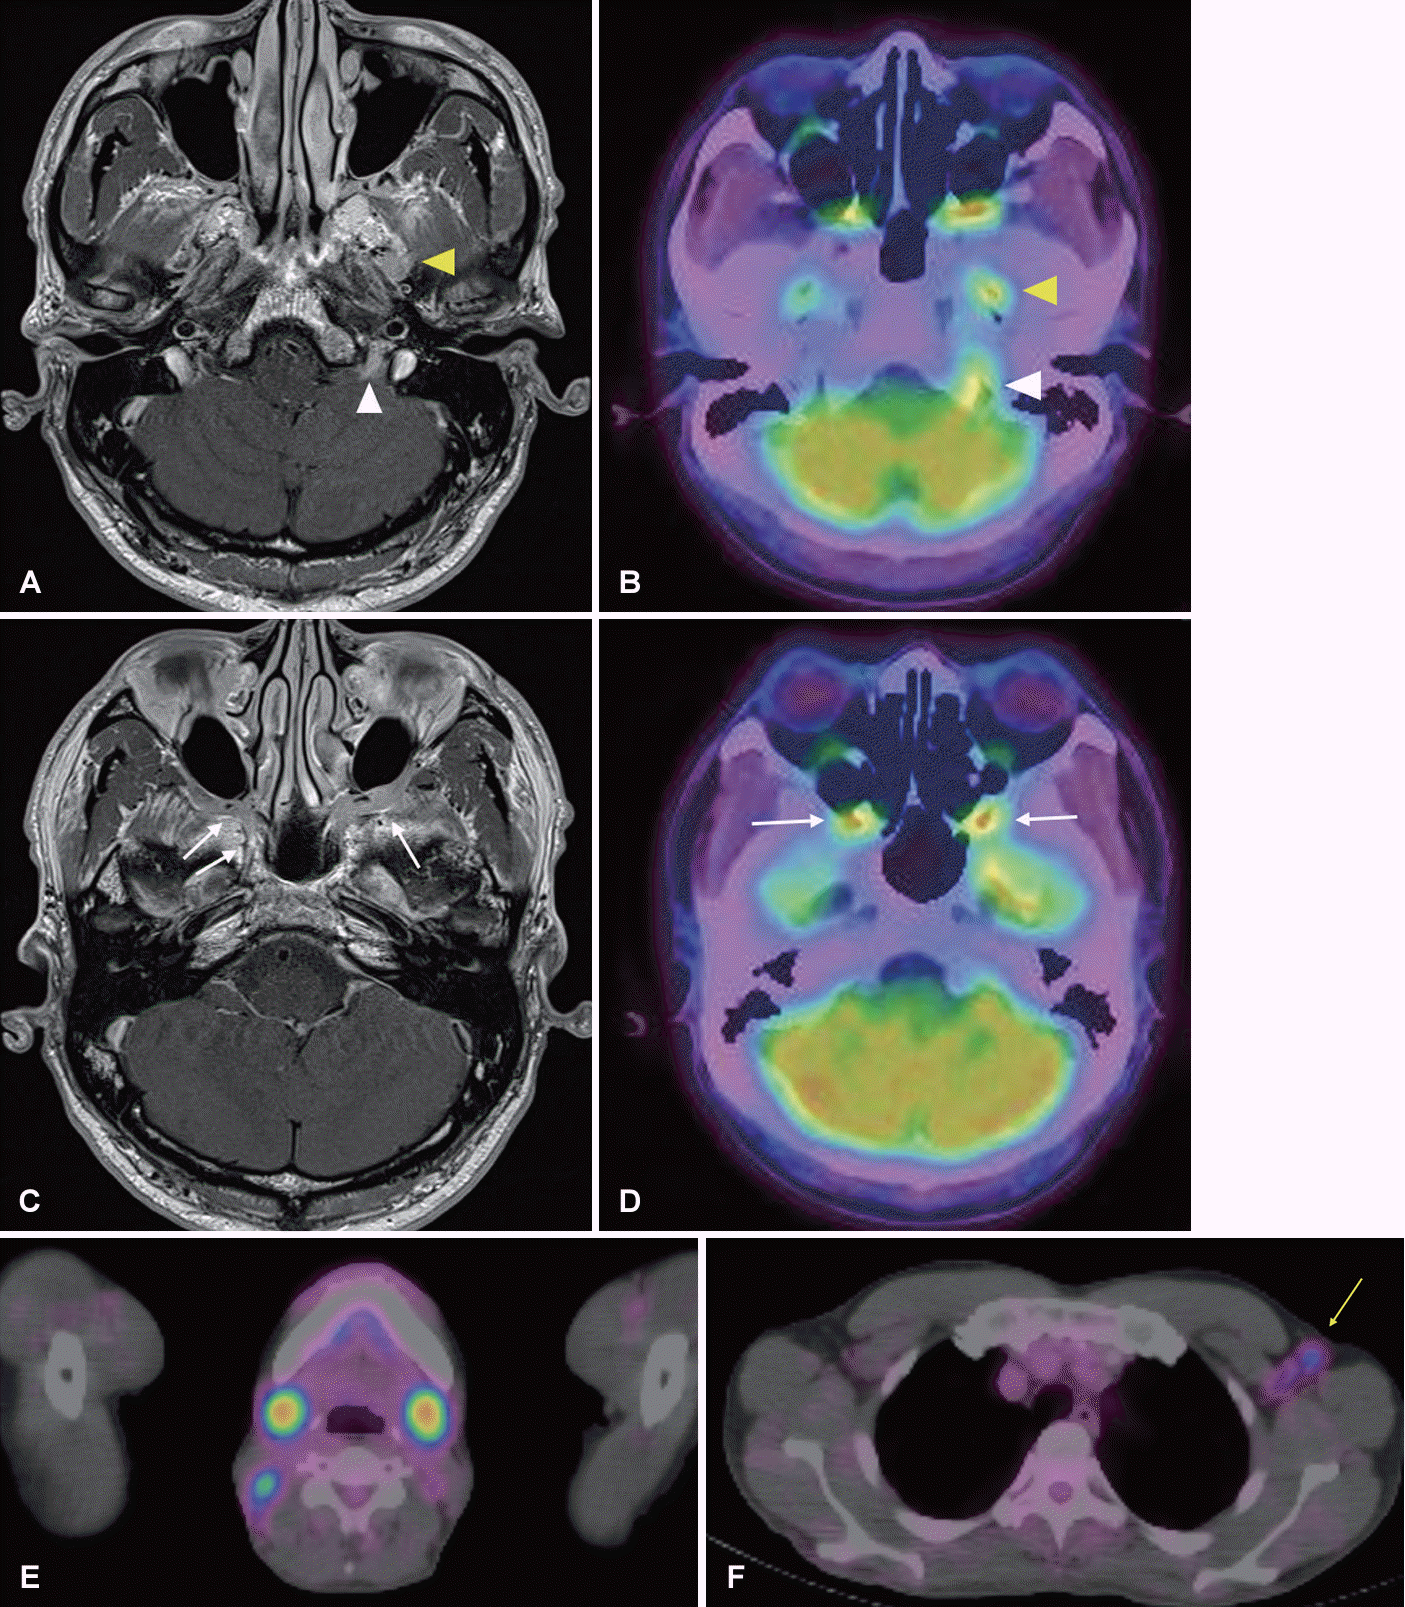

Evaluations to identify the etiology of MCN were conducted in a hospital setting. General laboratory tests and cerebrospinal fluid (CSF) analyses revealed normal findings on the day of admission. Contrast magnetic resonance imaging (MRI) was performed to evaluate the status of the involved cranial nerves. The MRI revealed a mass lesion with low-to-intermediate signal intensity on both T1 and T2 weighted images in the left jugular fossa, combined with pachymeningeal enhancement at the adjacent cerebellar convexity and internal auditory canal (Fig. 2A). Homogenous enhancement extended not only around the mass lesion, but also to both sides of the pterygopalatine fossa, retromaxillary fat pad, trigeminal nerve V2, and the pterygoid canal (Fig. 2C). Furthermore, enhancement of the left V3 route with a prominent left trigeminal nerve ganglion was observed (Fig. 2A). These MRI findings were consistent with the clinical symptoms and suggested the presence of a malignant tumor in the CNS [12]. Since the abnormality of bilateral SMGs on physical examination was concurrently accompanied by MCN, lymphoma was the initial candidate for MCN etiology rather than metastatic cancer.

Brain and whole-body positron emission tomography-computed tomography (PET-CT) were conducted and revealed hypermetabolic lesions with a maximum standard uptake value (maxSUV) of 3.4 in the left jugular fossa, both sides of foramen ovale and pterygopalatine fossa, which were consistent with the abnormal enhancement detected on MRI (Fig. 2B and D). In addition, hypermetabolic lesions on bilateral SMGs with a maxSUV of 9.7 and adjacent right cervical lymph nodes with a maxSUV of 5.5 were also observed (Fig. 2E). Incidentally, hypermetabolic lesions were also detected in the upper body greater curvature of the stomach (maxSUV of 2.3) (Fig. 3B) and left axillary lymph nodes (maxSUV 2.3) (Fig. 2F). As the stomach is commonly involved in lymphoma, esophagogastroduodenoscopy (EGD) was immediately performed within the preparation period for SMG resection for biopsy [13]. On EGD, multiple erythematous patches were observed in the greater curvature of the stomach, which were consistent with the hypermetabolic lesions observed on PET, and punch biopsies were performed at that site (Fig. 3A). The following day, an excisional biopsy of the right SMG and neck lymph nodes was performed. During surgery, a firmly palpated SMG was found to be severely adhered to the surrounding tissue.

Fig. 2.

MRI and PET-CT images. (A) Abnormal enhancement in left jugular fossa with max standard uptake value of 3.4 (white arrow head) and (B) left V3 with prominent trigeminal nerve ganglion of value of 3.4 (yellow arrowhead) were observed on MRI and PET-CT. (C) Abnormal enhancement in both pteryopalatine fossa, both retromaxillary fat pad, and both pterygoid canal (D) with max standard uptake value of 3.4 (white arrows) were observed on MRI and PET. (E) Hypermetabolic lesions on both SMG (maxSUV=9.7) and right cervical lymph nodes (maxSUV=5.5) respectively. (F) Hypermetablic lesions were observed in the upper body greater curvature of stomach (maxSUV=2.3) and left axillary lymph nodes (yellow arrow). SMG, submandibular gland; maxSUV, maximum standard uptake value.